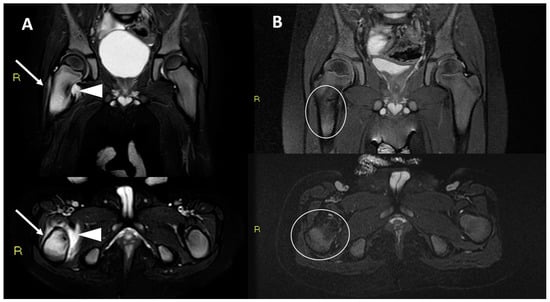

| 39 | 46 | Pain at night and muscular hypotrophy | Femur proximal metaphysis, cortical-periosteal | 10 mm | 15 mm | Yes | Yes | Non-diagnostic | 6 months after treatment: asymptomatic | N/A |